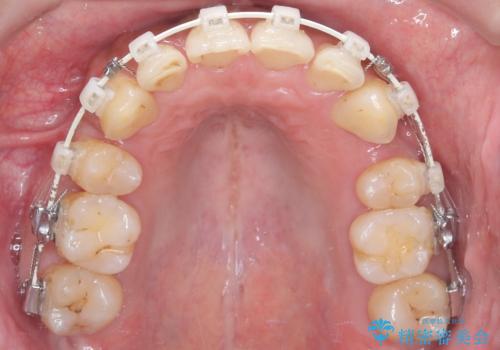

- 前歯のデコボコ(叢生)と、上下の歯の重なりが深い「ディープバイト(過蓋咬合)」を主訴にご来院されました。精密検査の結果、歯が並ぶスペースが不足しているため、上顎左右の小臼歯を抜歯することでスペースを確保し、全体の咬み合わせを改善する治療計画を立案しました。これにより、見た目の改善だけでなく、過度な咬み合わせによって生じる歯や顎への負担も軽減することを目指します。

今回の矯正治療では、まず歯が並ぶスペースを確保するため、上顎の小臼歯を抜歯しました。抜歯によってできたスペースを利用して前歯を奥へ移動させ、デコボコを解消。同時に、奥歯の咬み合わせを調整することで、深すぎた咬み合わせであるディープバイトも改善しました。治療の結果、長年気にされていた前歯のデコボコが解消され、理想的な歯並びに。さらに、正しい咬み合わせを獲得したことで、機能的にも安定した美しい口元になりました。